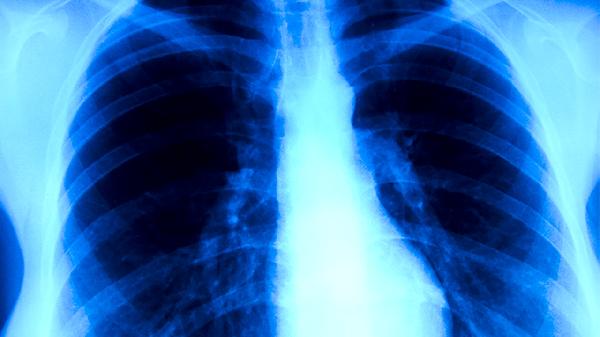

细菌性肺炎主要由肺炎链球菌、金黄色葡萄球菌等致病菌感染引起,常见症状包括高热、铁锈色痰和呼吸急促。胸部X线可见肺叶实变影,血常规检查显示白细胞升高。治疗需遵医嘱使用阿莫西林克拉维酸钾片、头孢呋辛酯片或左氧氟沙星片等抗生素,同时需卧床休息并加强营养支持。

病毒性肺炎多由流感病毒、呼吸道合胞病毒等引发,表现为干咳、肌肉酸痛和低热,胸部CT可见磨玻璃样改变。确诊需进行病毒核酸检测,治疗可选用奥司他韦胶囊、扎那米韦吸入粉雾剂等抗病毒药物,合并细菌感染时需联用抗生素。患者应保持室内空气流通并多饮水。

真菌性肺炎多见于免疫功能低下者,曲霉菌和隐球菌是常见病原体,CT可见结节伴晕征。诊断依赖痰培养或G试验,治疗需使用氟康唑胶囊、伏立康唑片等抗真菌药物,疗程较长。患者需严格控制血糖,避免接触霉变环境,定期复查肝肾功能。

吸入性肺炎常发生于吞咽功能障碍患者,因误吸食物或胃内容物导致,表现为突发呛咳伴低氧血症。胸部影像学显示右下肺浸润影,治疗需用头孢哌酮舒巴坦钠注射液联合甲硝唑氯化钠注射液抗感染。护理时应抬高床头30度进食,进行吞咽功能训练预防复发。